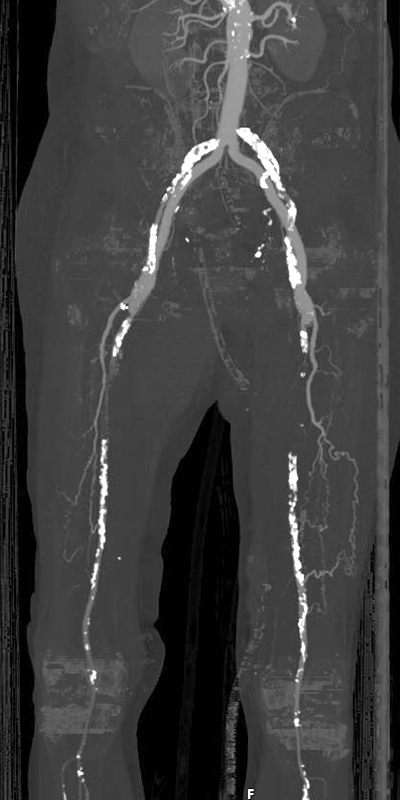

claudication   quantitative imaging laboratory 400×800 claudication quantitative imaging laboratory from 3dqlab.stanford.edu